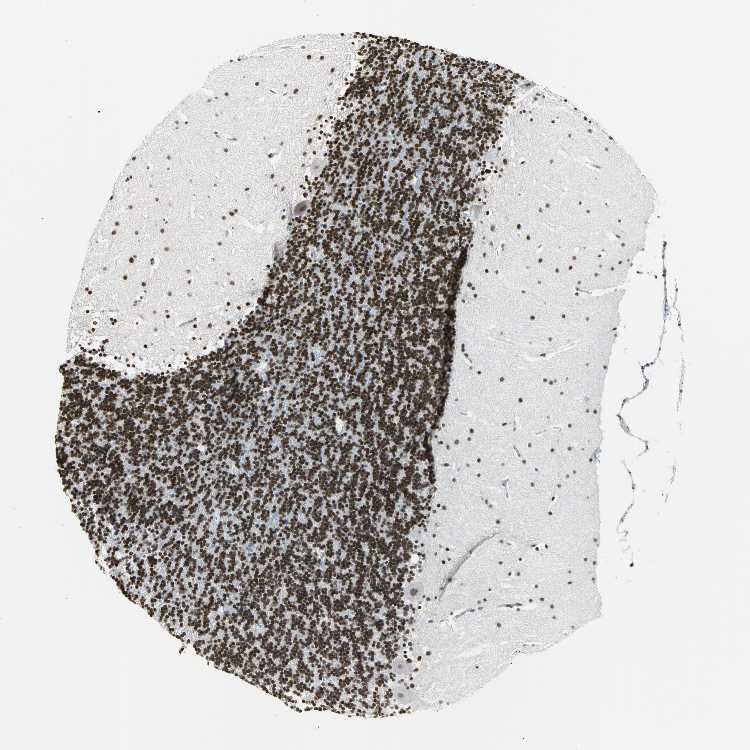

CEREBELLUM - Antibody stainingi

Antibody staining in the annotated cell types in the current human tissue is reported as not detected, low, medium, or high, based on conventional immunohistochemistry profiling in selected tissues. This score is based on the combination of the staining intensity and fraction of stained cells.

Each image is clickable and will lead to virtual microscopy that enables deeper exploration of all samples and also displays staining intensity scores, fraction scores and subcellular localization as well as patient and tissue information for each sample.

Antibody HPA004911

Purkinje cells Medium

Cells in granular layer High

Cells in molecular layer High